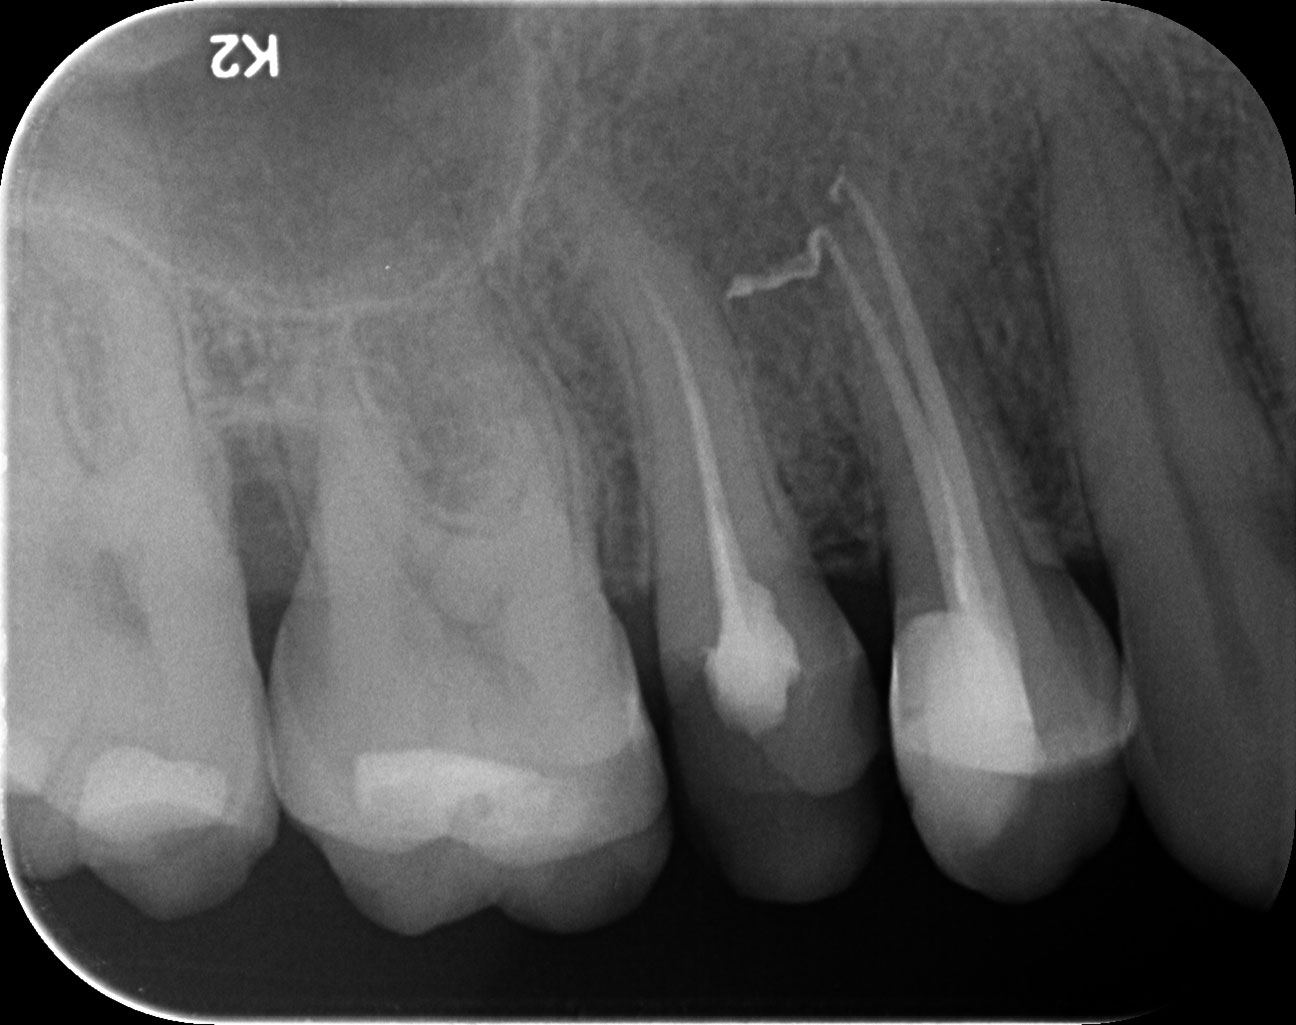

Dantų kanalų gydymas